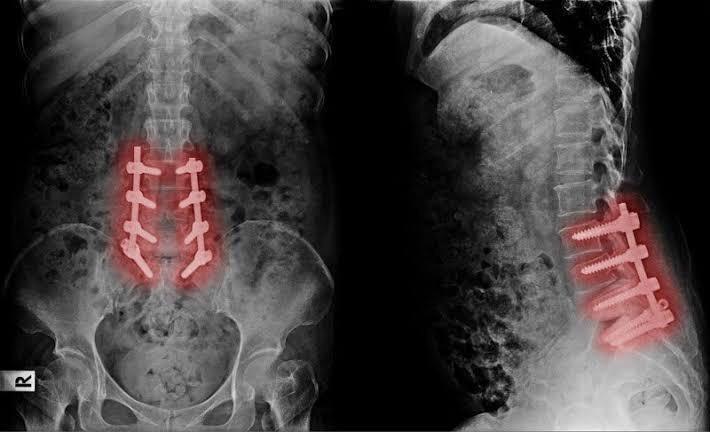

Failed back surgery syndrome (FBSS) is defined by the International Association for the Study of Pain as lumbar spinal pain of unknown origin either persisting despite surgical intervention or appearing after surgical intervention for spinal pain originally in the same topographical location.